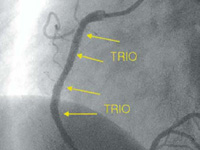

TRIO

TRIO is the first on the market multi-drug eluting stent where nano-layers of different drugs are assembled on DLC platform.

Before implantation |

After implantation |